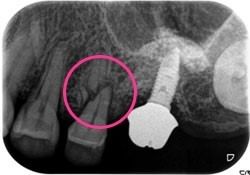

症例4【50代女性】左上6 副鼻腔膜を挙上しインプラント埋入 左上5 歯根破折の為インプラント埋入

治療前

左上5の歯根破折

主訴 左上奥歯で物が噛めない。入れ歯は煩わしいので、インプラントを希望。

左上第一大臼歯欠損部位は、骨の高さが3~4㎜しかなく、造骨の為にソケットリフト(骨造成)を行い、骨の高さを確保しインプラントを埋入。

約半年の免荷期間を経て、仮歯を装着、リハビリをし、約7ヶ月後にメタルボンド(金属焼付ポーセレン)を装着。

その後、左上第二小臼歯の歯根破折の為に、2本目のインプラントを埋入。(抜歯即時埋入)

リスクとしては、ソケットリフト(骨造成)による一過性の副鼻腔炎が起きる可能性がある。まれに洞底膜が破れる可能性がある。ただし、膜は約3週で再生するので、膜の回復を待ち、再オペを行う。

費用 111万(オペ。ソケットリフト・人工骨・採血による濃縮血小板生成・仮歯・最終補綴物まで含む)